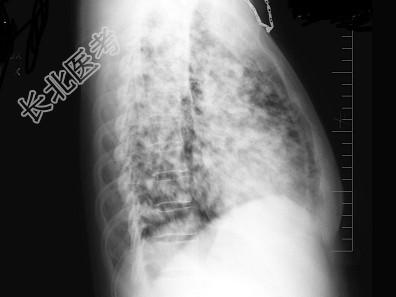

- 单项选择题女,52岁, 感胸痛2月余,无发热, X线检查如图,最可能的诊断是 ( )

A、细支气管肺泡癌

B、两肺炎症

C、亚急性血行播散型肺结核

D、肺转移瘤

E、结节病